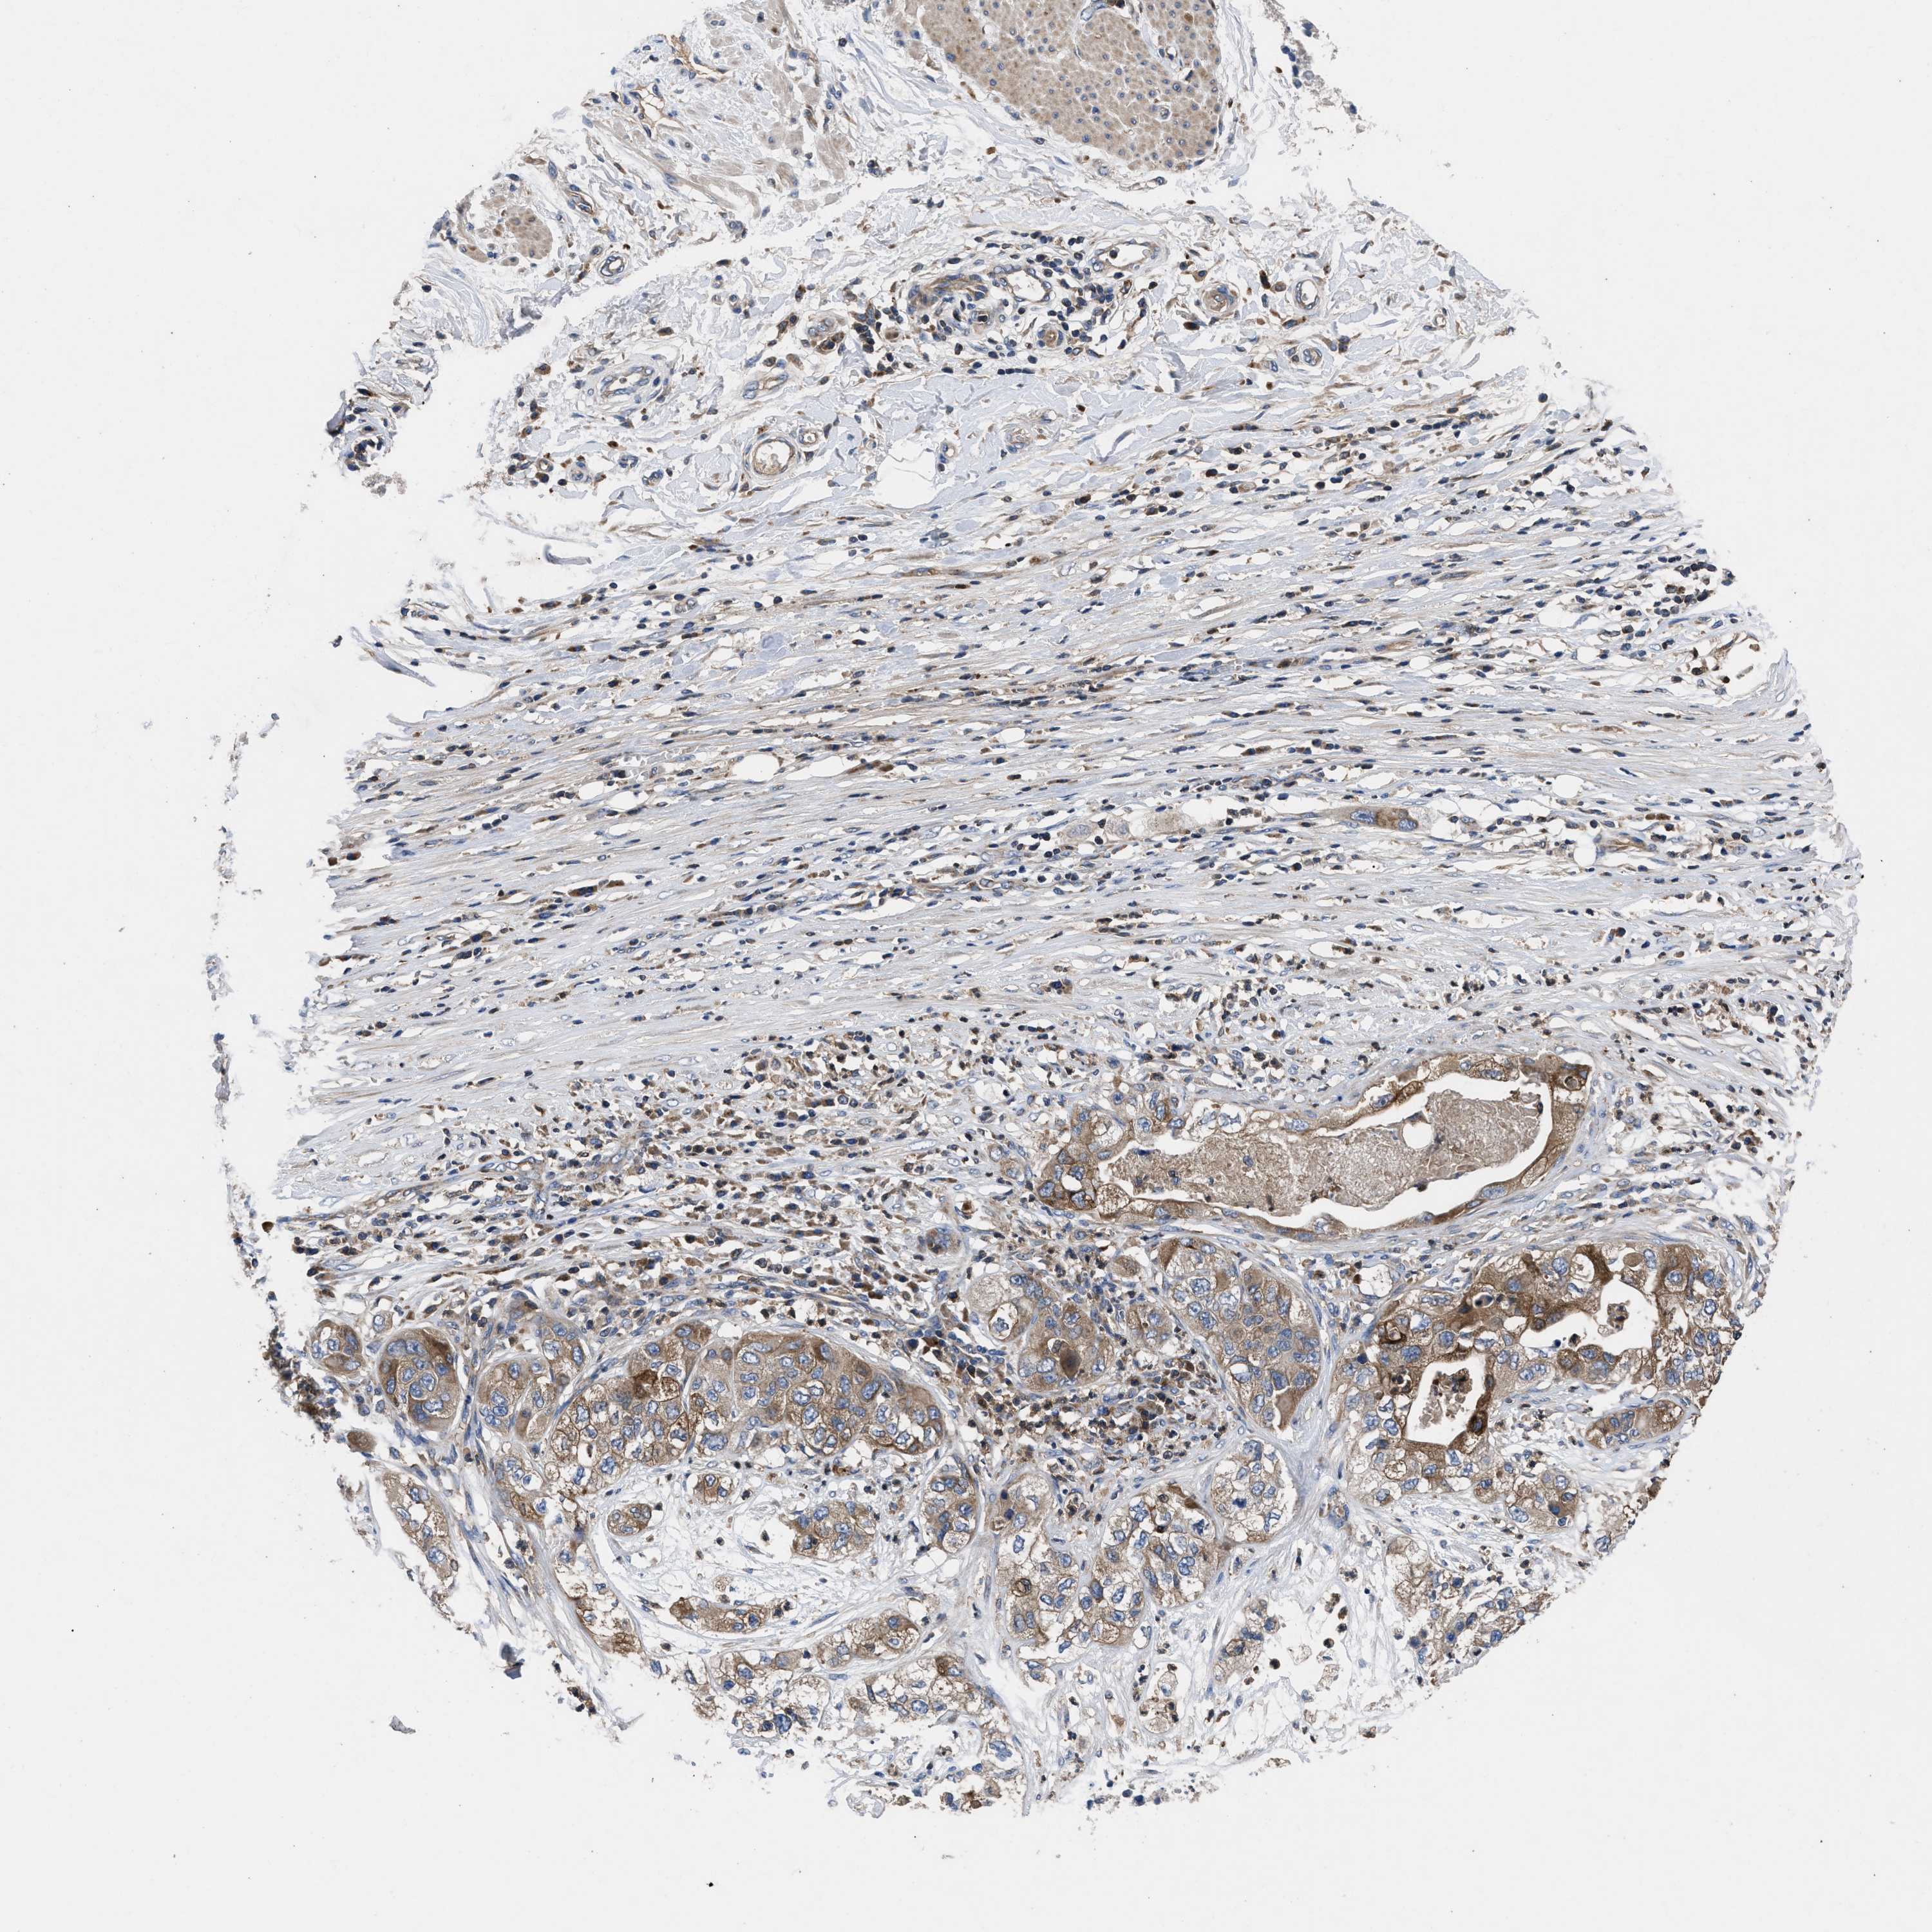

PANCREATIC CANCER - Protein expressioni

A mouse-over function shows sample information and annotation data. Click on an image to view it in a full screen mode. Samples can be filtered based on level of antibody staining by selecting one or several of the following categories: high, medium, low and not detected. The assay and annotation is described here.

Note that samples used for immunohistochemistry by the Human Protein Atlas do not correspond to samples in the TCGA dataset.

Antibody stainingi

Antibody staining in the annotated cell types in the current human tissue is reported as not detected, low, medium, or high, based on conventional immunohistochemistry profiling in selected tissues. This score is based on the combination of the staining intensity and fraction of stained cells.

Each image is clickable and will lead to virtual microscopy that enables deeper exploration of all samples and also displays staining intensity scores, fraction scores and subcellular localization as well as patient and tissue information for each sample.

Antibody HPA018162

Staining

High

Medium

Low

Not detected

Intensity

Strong

Moderate

Weak

Negative

Quantity

>75%

75%-25%

<25%

None

Location

Nuclear

Cytoplasmic/membranous

Cytoplasmic/membranous,nuclear

Adenocarcinoma, NOS